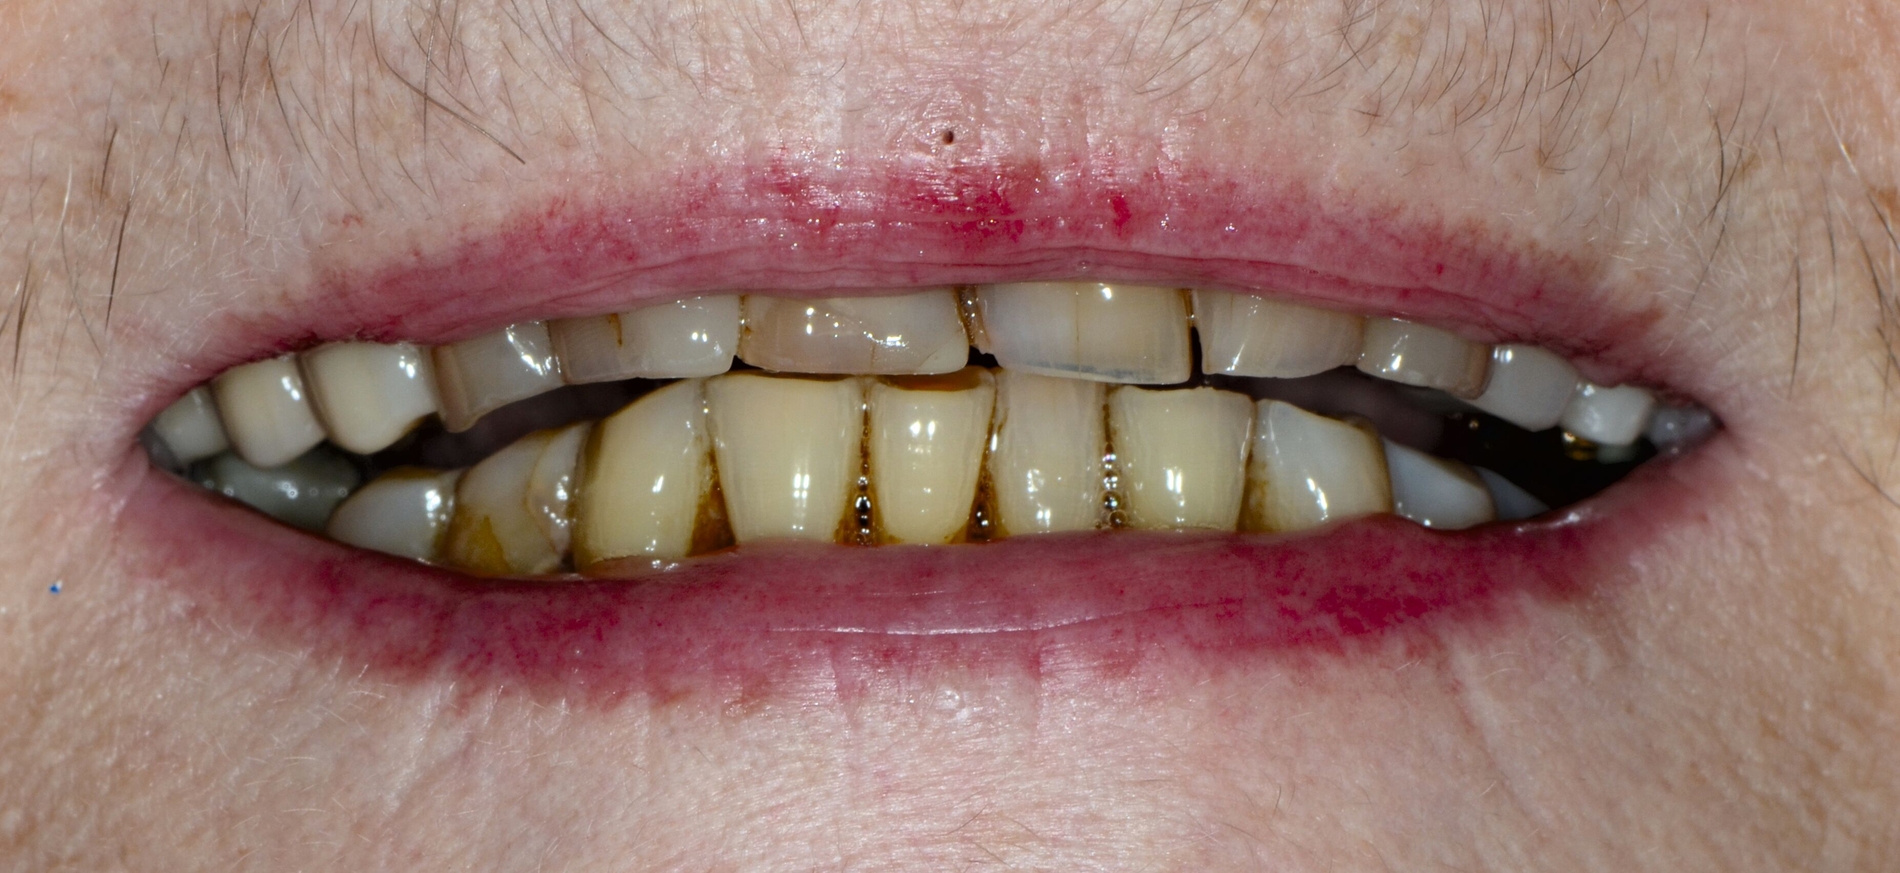

... für Zahnformkorrekturen im Frontzahnbereich

Ähnliche Ergebnisse wurden bei Zahnformkorrekturen erzielt. Die untersuchten Studien berichteten über hohe bis sehr hohe Überlebensraten von Komposit-Restaurationen mit Nachbeobachtungen bis zu 15 Jahren. Beim Vergleich mit indirekten Keramikveneers zeigten diese zwar höhere Überlebensraten, doch basiert diese Schlussfolgerung auf einer einzelnen Studie mit kurzer Nachbeobachtungszeit [Meijering et al., 1998]. Die Nutzen-Schaden-Bewertung spricht klar für den Einsatz von Kompositen zur Zahnformkorrektur im Frontzahnbereich (Abbildung 3), aufgrund der hohen Überlebensraten, der guten bis ausgezeichneten klinischen Qualität, der Reparierbarkeit und der geringeren Invasivität im Vergleich zu Keramikveneers. Der elektive Charakter dieser Verfahren sollte bei der Gesamtbeurteilung berücksichtigt werden. Für diese Behandlungen wird ein minimalinvasiver oder nichtinvasiver und präventionsorientierter Ansatz empfohlen.